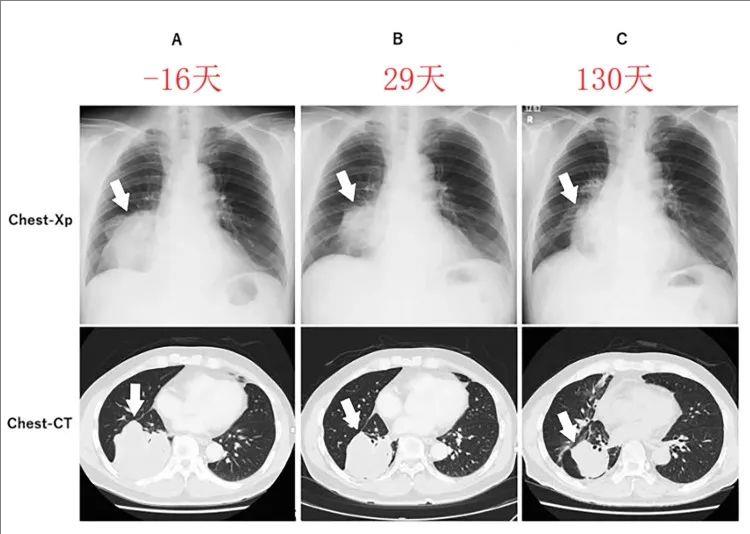

1个月实现完全缓解!"神奇"抗癌药让全球首例ETV6-NTR

接受各种治疗后病情仍在疯狂进展,肿瘤全身扩散的晚期罕见肺癌患者,在接受一款“神奇”抗癌药治疗后,仅一个月左右,所有转移性肺病灶实现完全缓解,并且已持续1年以上。...